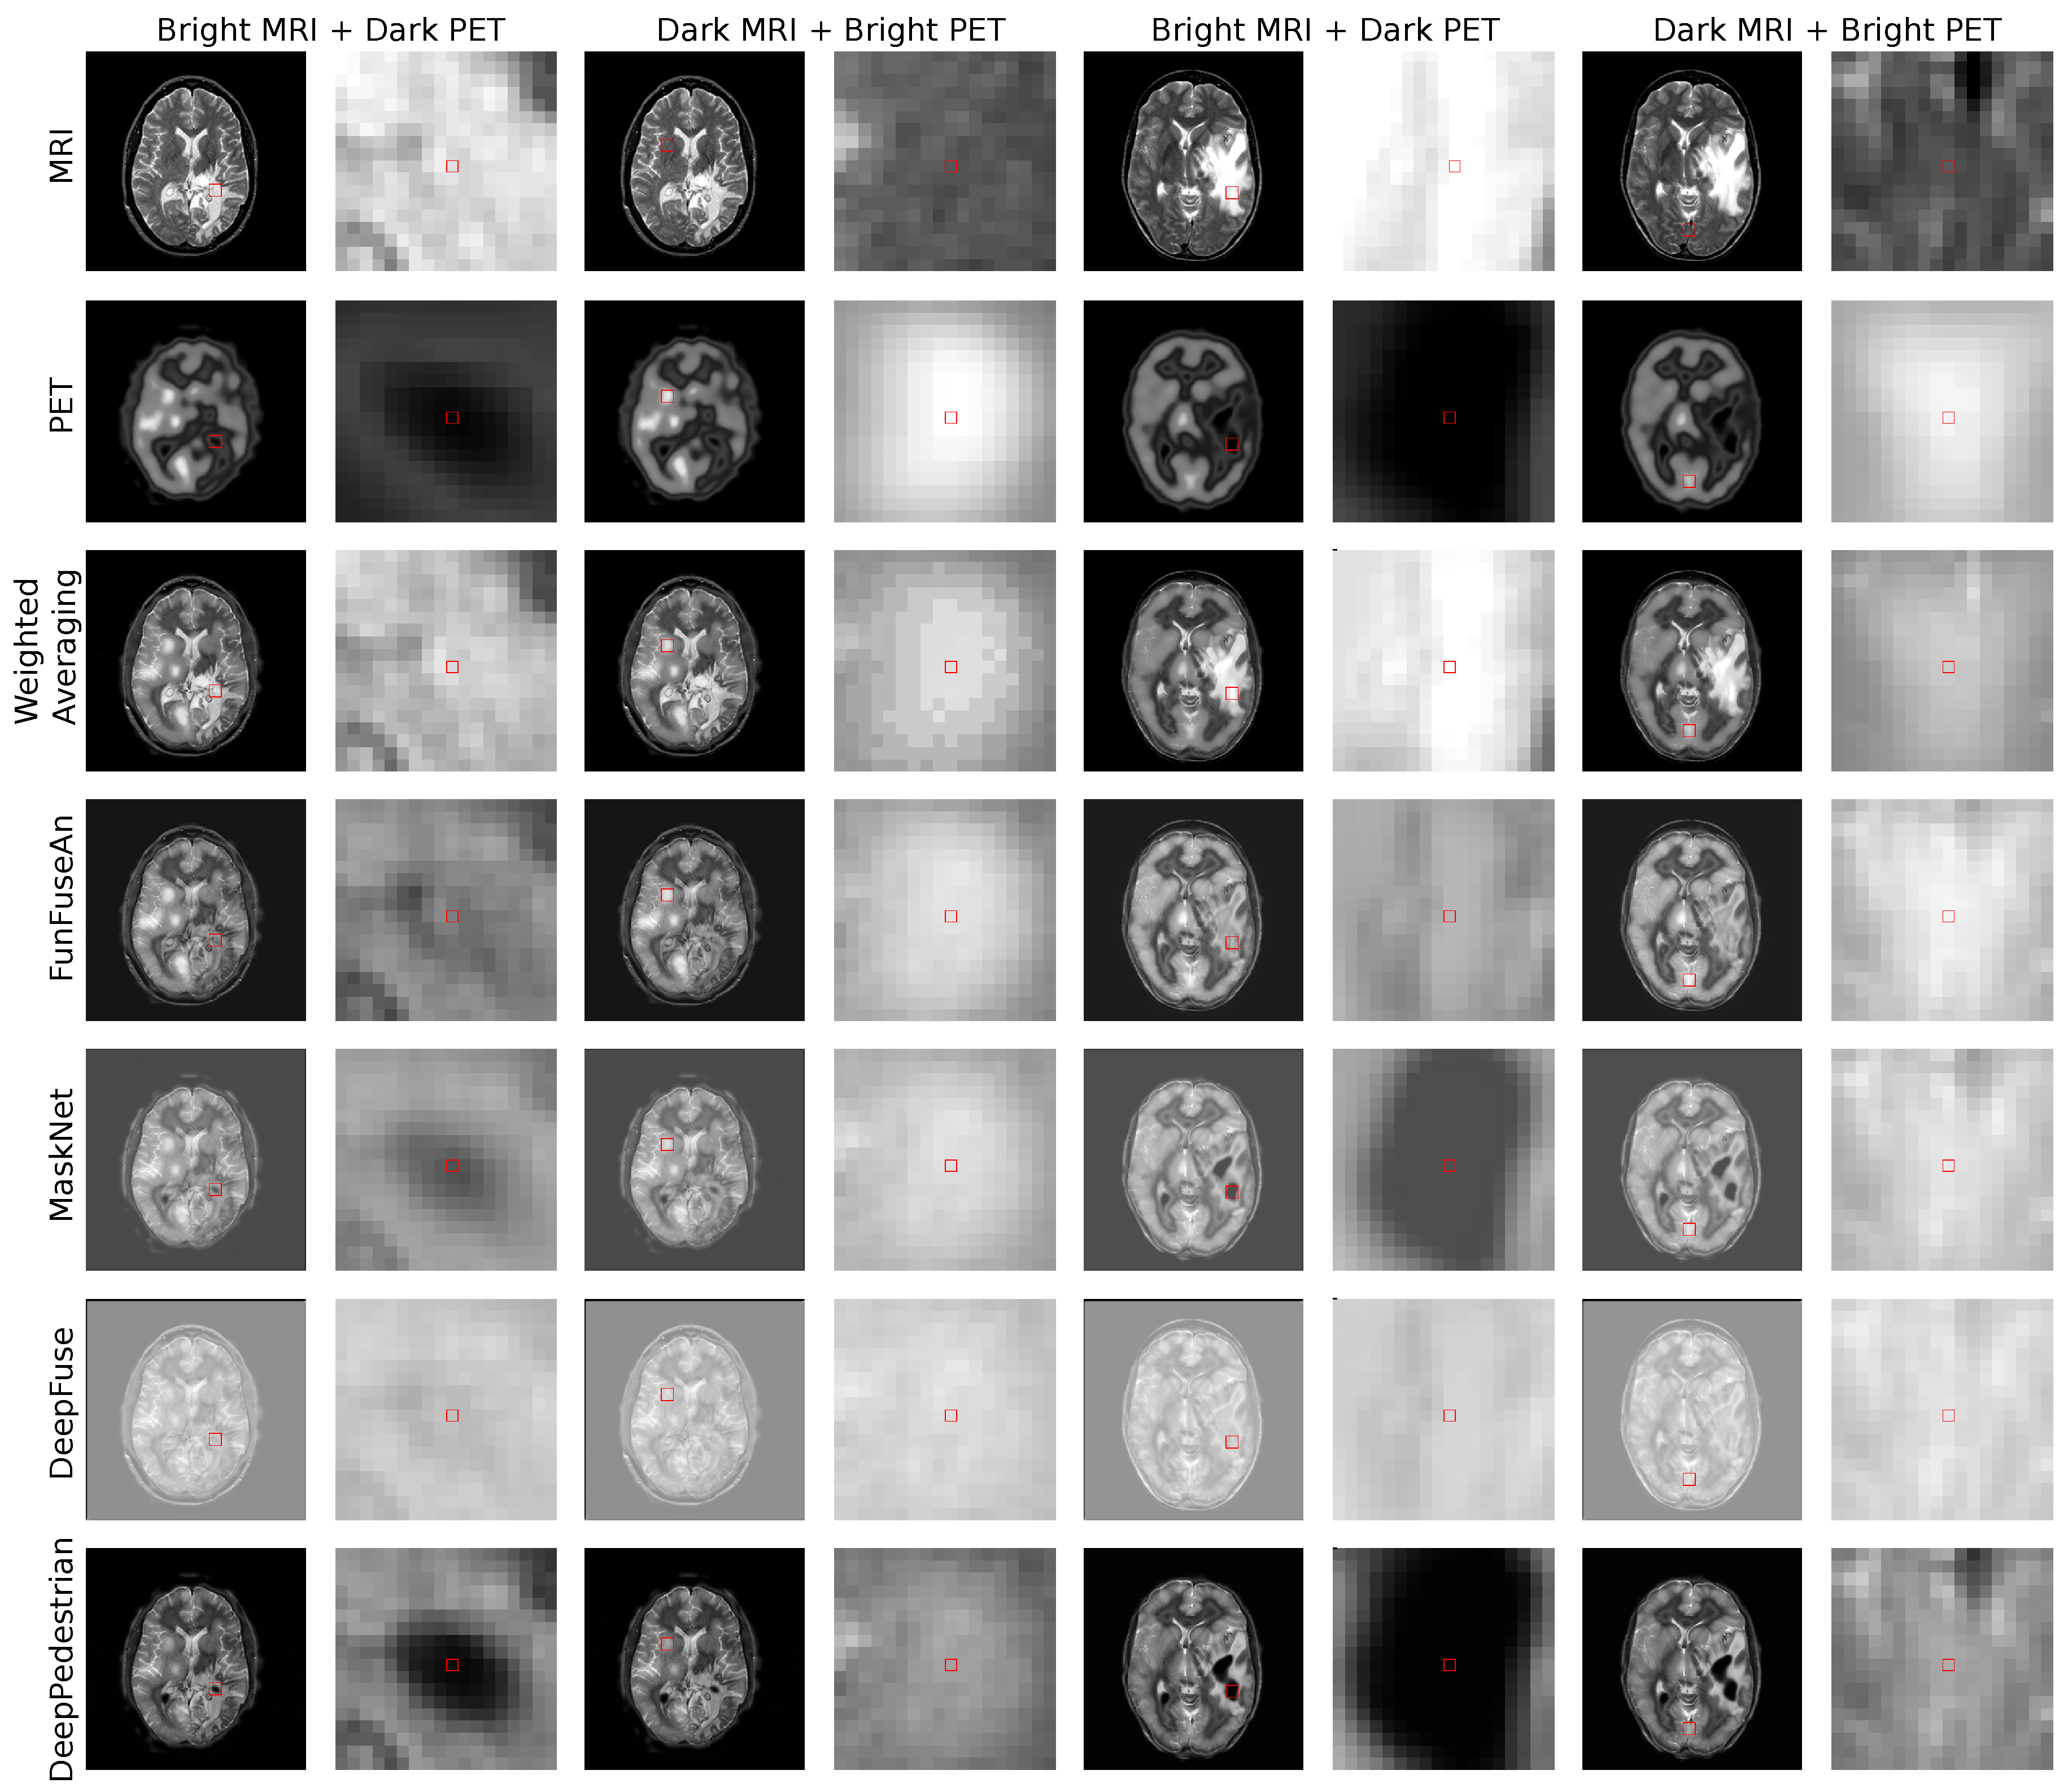

5.2. Clinical Test Examples

The clinical test examples were acquired from Harvard Whole Brain Atlas database [73] with the combination of MRI-T2 and PET/SPECT images from patients suffering from different types of glioma. The test examples were disjoint to the training dataset and the network has not seen such clinical pathology during its training. The first clinical MRI-PET image pair is shown in the first four columns of Figure 4. The scans are of a patient who was suffering from Anaplastic Astrocytoma, a rare and malignant brain lesion classified under the category of high-grade glioma. A lesion in the right and the left side of the brain is visible in the MRI image and has bright grayscale intensities. On the other hand, bright regions in the PET image convey normal blood flow while very dark regions suggest no blood flow in the necrotic tissues. In the second clinical MRI-PET image pair as shown in the last four columns in Figure 4, the patient had a long history of tobacco usage and was originally suffering from Metastatic Bronchogenic Carcinoma, which is a type of lung cancer. The patient began having headaches and the scans revealed brain metastases that occurred due to the spread of cancer cells present in the lungs to the brain resulting in the diagnosis of glioma. A lesion in the right side of the brain with bright features is visible in the MRI image while very dark PET features reveal no blood flow in the necrotic region.

6.1. Fused Images

The fused images of the Weighted Averaging method as shown in the third row of Figure 4 gives very high weightage to the bright input intensities in the regions where intensities in the other modality are darker. Therefore, we can perceive a reproduction of features from relatively brighter regions of the MRI and PET images due to which Weighted Averaging method is unable to preserve the clinically important dark PET features related to the necrotic core but favorably preserves the bright PET features resembling healthy tissues. The fused images of the FunFuseAn as shown in the fourth row of Figure 4 are comparatively similar to the Weighted Averaging approach where it is not able to preserve the very dark PET features. However, the fused images from FunFuseAn look relatively dull compared to the fused images from Weighted Averaging since the FunFuseAn network mixes both MRI and PET features even though the boundary information about the necrotic region is lost.

The analysis of the fused images from MaskNet in the fifth row of Figure 4 shows a significant loss of anatomical edges from MRI such as the brain skull. However, contrary to Weighted Averaging and FunFuseAn, MaskNet preserved the PET features better in both the dark and bright regions resembling the necrotic core and healthy tissues, respectively. However, the dark PET features are slightly blurred due to changes in the overall brightness of the fused image. The fused image obtained from DeepFuse as shown in the sixth row of Figure 4 has an even higher shift in grayscale intensities due to which the method is unable to preserve the dark PET features even though the overall anatomical MRI structures are well preserved. The change in brightness can be explained by the fact that the L 2 M R I and L 2 P E T converged at higher loss values compared to other networks due to which the brightness component of SSIM was not properly optimized. Additionally, the architecture of DeepFuse network has been crafted for adding exposure to underexposed images by using the brightness component from each of the input image modalities and employ it to generate very bright fusion results. The fused image from DeepPedestrian as shown in the seventh row of Figure 4 clearly delineates the boundary of the necrotic core by preserving the very dark PET features, which is of high clinical significance for medical professionals. However, the anatomical edges from MRI are lost in the fused image which is also one of the main artifacts in the MaskNet network. Another important observation is that the bright PET features resembling healthy tissues appear to be not well preserved due to an overall brightness shift.

6.2. Guidance Images

In this section, we analyze the fusion methods with respect to its sensitivity to feature level changes in the input images by visualizing the Guidance MRI and Guidance PET images in Figure 5 and Guidance RGB images in Figure 6 for the two clinically relevant regions. We chose the first region as bright MRI with very dark PET features since it is the region that contains the necrotic core of glioma which clinicians are interested to operate for resection. The second region of interest has dark MRI with bright PET features resembling healthy tissues which is interesting for the visualization of high brain activity due to external stimuli. Ideally, a guidance MRI image should have low gradients meaning a fusion method should be less sensitive to changes in both dark and bright MRI regions.

6.2.1. Weighted Averaging

For the region with bright MRI and dark PET intensities in both the test examples, it can be observed that the guidance MRI image is significantly brighter than the guidance PET image, revealing higher sensitivity to changes in MRI features. This suggests that a small change in the MRI pixel intensities will sharply modify the fused pixel intensities while it requires a substantial alteration in the PET pixel intensities to hold a considerable effect on the fused pixel intensities. This is an undesired outcome as a fusion method should be stable to changes in the pixel intensities of MRI. The guidance RGB image shows magenta color in these regions as the red channel containing guidance MRI image has high gradients and the blue channel containing the fused image have high pixel intensities compared to the green channel containing the guidance PET image with low gradients. On the other hand, the region with dark MRI and bright PET intensities shows an adverse effect where the guidance PET image is relatively brighter compared to the guidance MRI image since higher weightage is now given to the bright PET grayscale values. The guidance RGB image in this region shows cyan color since the green channel with guidance PET image has high gradients while the blue channel with the fused image also has higher intensities.

6.2.2. FunFuseAn

For the region with bright MRI and dark PET intensities, there are higher gradients in the guidance MRI image compared to the guidance PET image. This conveys that the fused pixels within the necrotic core have a higher sensitivity to changes in the MRI pixels. The guidance RGB image also shows red color within the necrotic region indicating only the guidance MRI have high intensities compared to the images in other color channels. For the region with dark MRI and bright PET intensities, the guidance MRI and guidance PET images have low gradients. This means that the fused pixels in this region are quite stable to changes in the MRI and PET pixel intensities. Hence, the color in the guidance RGB image is predominantly blue as the fused pixel intensities are higher than the gradient values in both the guidance images. Therefore, it is challenging to interpret which of the two input modalities has a higher influence on the fused image in this particular region.

6.2.3. DeepFuse

In the bright MRI and dark PET region resembling necrotic core, there are relatively high gradient values in the guidance MRI image compared to the guidance PET image. This is the reason for the shades of magenta in the guidance RGB image. For the dark MRI and bright PET intensity region in the first test example, the pattern is similar where there are higher gradients in the guidance MRI image compared to the guidance PET image due to which magenta color is visible in the guidance RGB image. For the second test example, however, the guidance images from both MRI and PET have low gradients indicating a low influence of change in input pixel intensities within this region. Hence, the guidance RGB image also appears to be light blue in color in this region.

6.2.4. MaskNet and DeepPedestrian

For the necrotic region with bright MRI and dark PET intensities in the first test example, the guidance PET image is relatively brighter than the guidance MRI image for both MaskNet and DeepPedestrian networks. This conveys that both the networks are highly sensitive to the changes in very dark PET intensities of the necrotic region compared to the changes in MRI intensities. Since both the guidance MRI and the fused image have low intensities compared to the guidance PET image in this region, the guidance RGB image exhibits green color. However, for the second test example, both the guidance images have very low gradients in the same region, showcasing the stability of the networks for pixel intensity changes in this region. Since all the color channels in the guidance RGB image have low intensities, the guidance RGB image does not have a fixed color scheme and is dark. For the region with dark MRI and bright PET intensities, however, the behavior is similar in both the test examples where both the guidance images have low gradients due to which it is challenging to differentiate the influence of each of the modalities while the MaskNet network has learned the bright PET features better, leading to blue color in the guidance RGB image.

6.2.5. Summary

The guidance images provided a static overview of the influence of input principle pixel on the fused principle pixel and assisted in visualizing which of the two modalities has higher influence in the clinical region of interest. Therefore, it provided new insights related to the stability of fusion networks in these regions which were not perceivable by looking at the fused images. The guidance images clearly show that MaskNet and DeepPedestrian networks performed very differently compared to other fusion methods. For the region with the dark PET features resembling necrotic core, all the methods except MaskNet and DeepPedestrian were sensitive to changes in the bright MRI intensities which is not suitable for a reliable analysis of the necrotic tumor boundary since the dark PET features might not be properly preserved in the fused image due to changes in the MRI features. Both MaskNet and DeepPedestrian preserved the dark PET features in the fused image and were quite stable to the changes in the MRI pixel intensities due to which both these methods are far more suitable for the clinical application than any other fusion methods. However, the guidance images do not reveal the influence of neighborhood pixels on the fused principle pixel which is important for estimating a better fusion approach between the two of these networks.